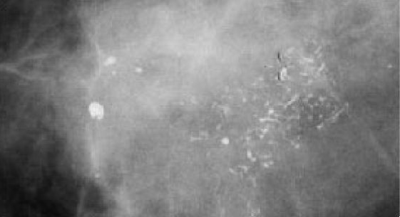

As microcalcificações pleomórficas, como as demonstradas abaixo, devem classificar a mamografia em qual das categorias da padronização de laudos BI-RADS?

A

3

B

4a

C

4b

D

5

E

6